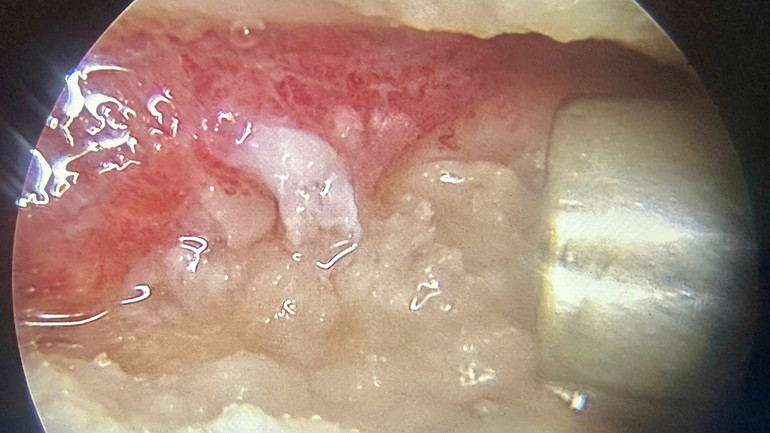

វេជ្ជបណ្ឌិតបានអនុវត្តការកំទេចកំទី arthroscopic និងការសម្អាតសន្លាក់ ក្នុងពេលដំណាលគ្នាអនុវត្ត Platelet Rich Fibrin (PRF) - កាវស្វ័យប្រវត្តិដែលស្រង់ចេញពីឈាមរបស់អ្នកជំងឺ។

ពី 240ml នៃឈាមគ្រឿងកុំព្យូទ័ររបស់អ្នកជំងឺ វេជ្ជបណ្ឌិតបានស្រង់ចេញ 10.9ml នៃ PRF បន្ទាប់មកចាក់វាដោយផ្ទាល់ទៅក្នុងកន្លែងដែលរងការខូចខាតអំឡុងពេល arthroscopy នៃជង្គង់ទាំងពីរ។